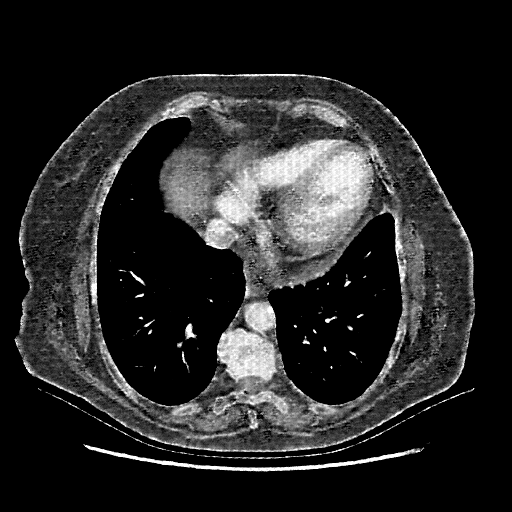

Targeted Slice 70 - Mediastinum Window Analysis (Generated vs Real Venous)

0.645

Mediastinum SSIM

47.0

Mediastinum RMSE

20.6

Mediastinum MAE

Average Mediastinum Window Metrics Across All Slices (101 slices) - Generated vs Real Venous

0.623

Mediastinum SSIM (Avg)

47.6

Mediastinum RMSE (Avg)

21.9

Mediastinum MAE (Avg)

Original VENOUS CT scan

Mediastinum window (WL 40, WW 400 β†’ Low βˆ’160, High +240)